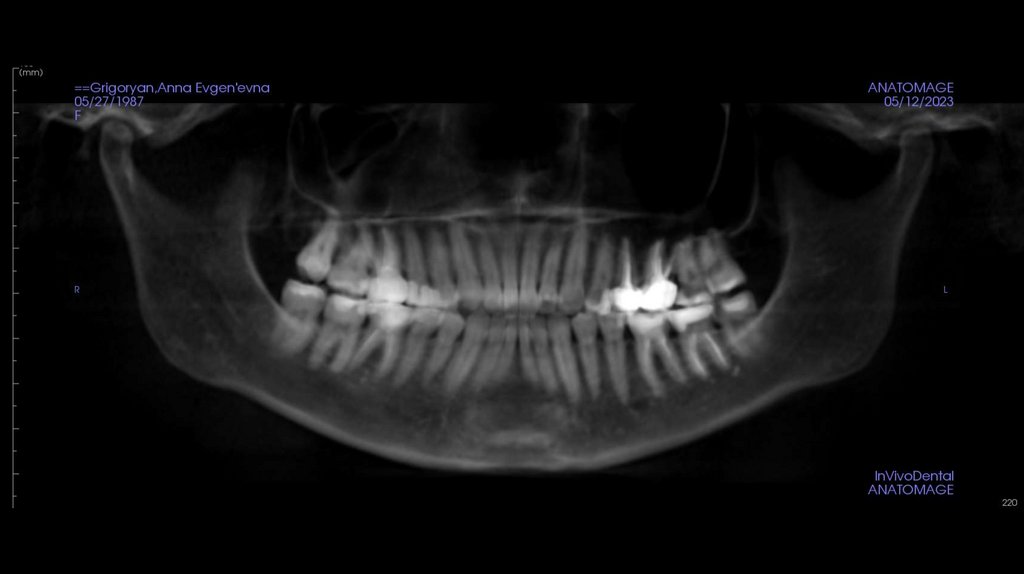

12.

ОПТГ